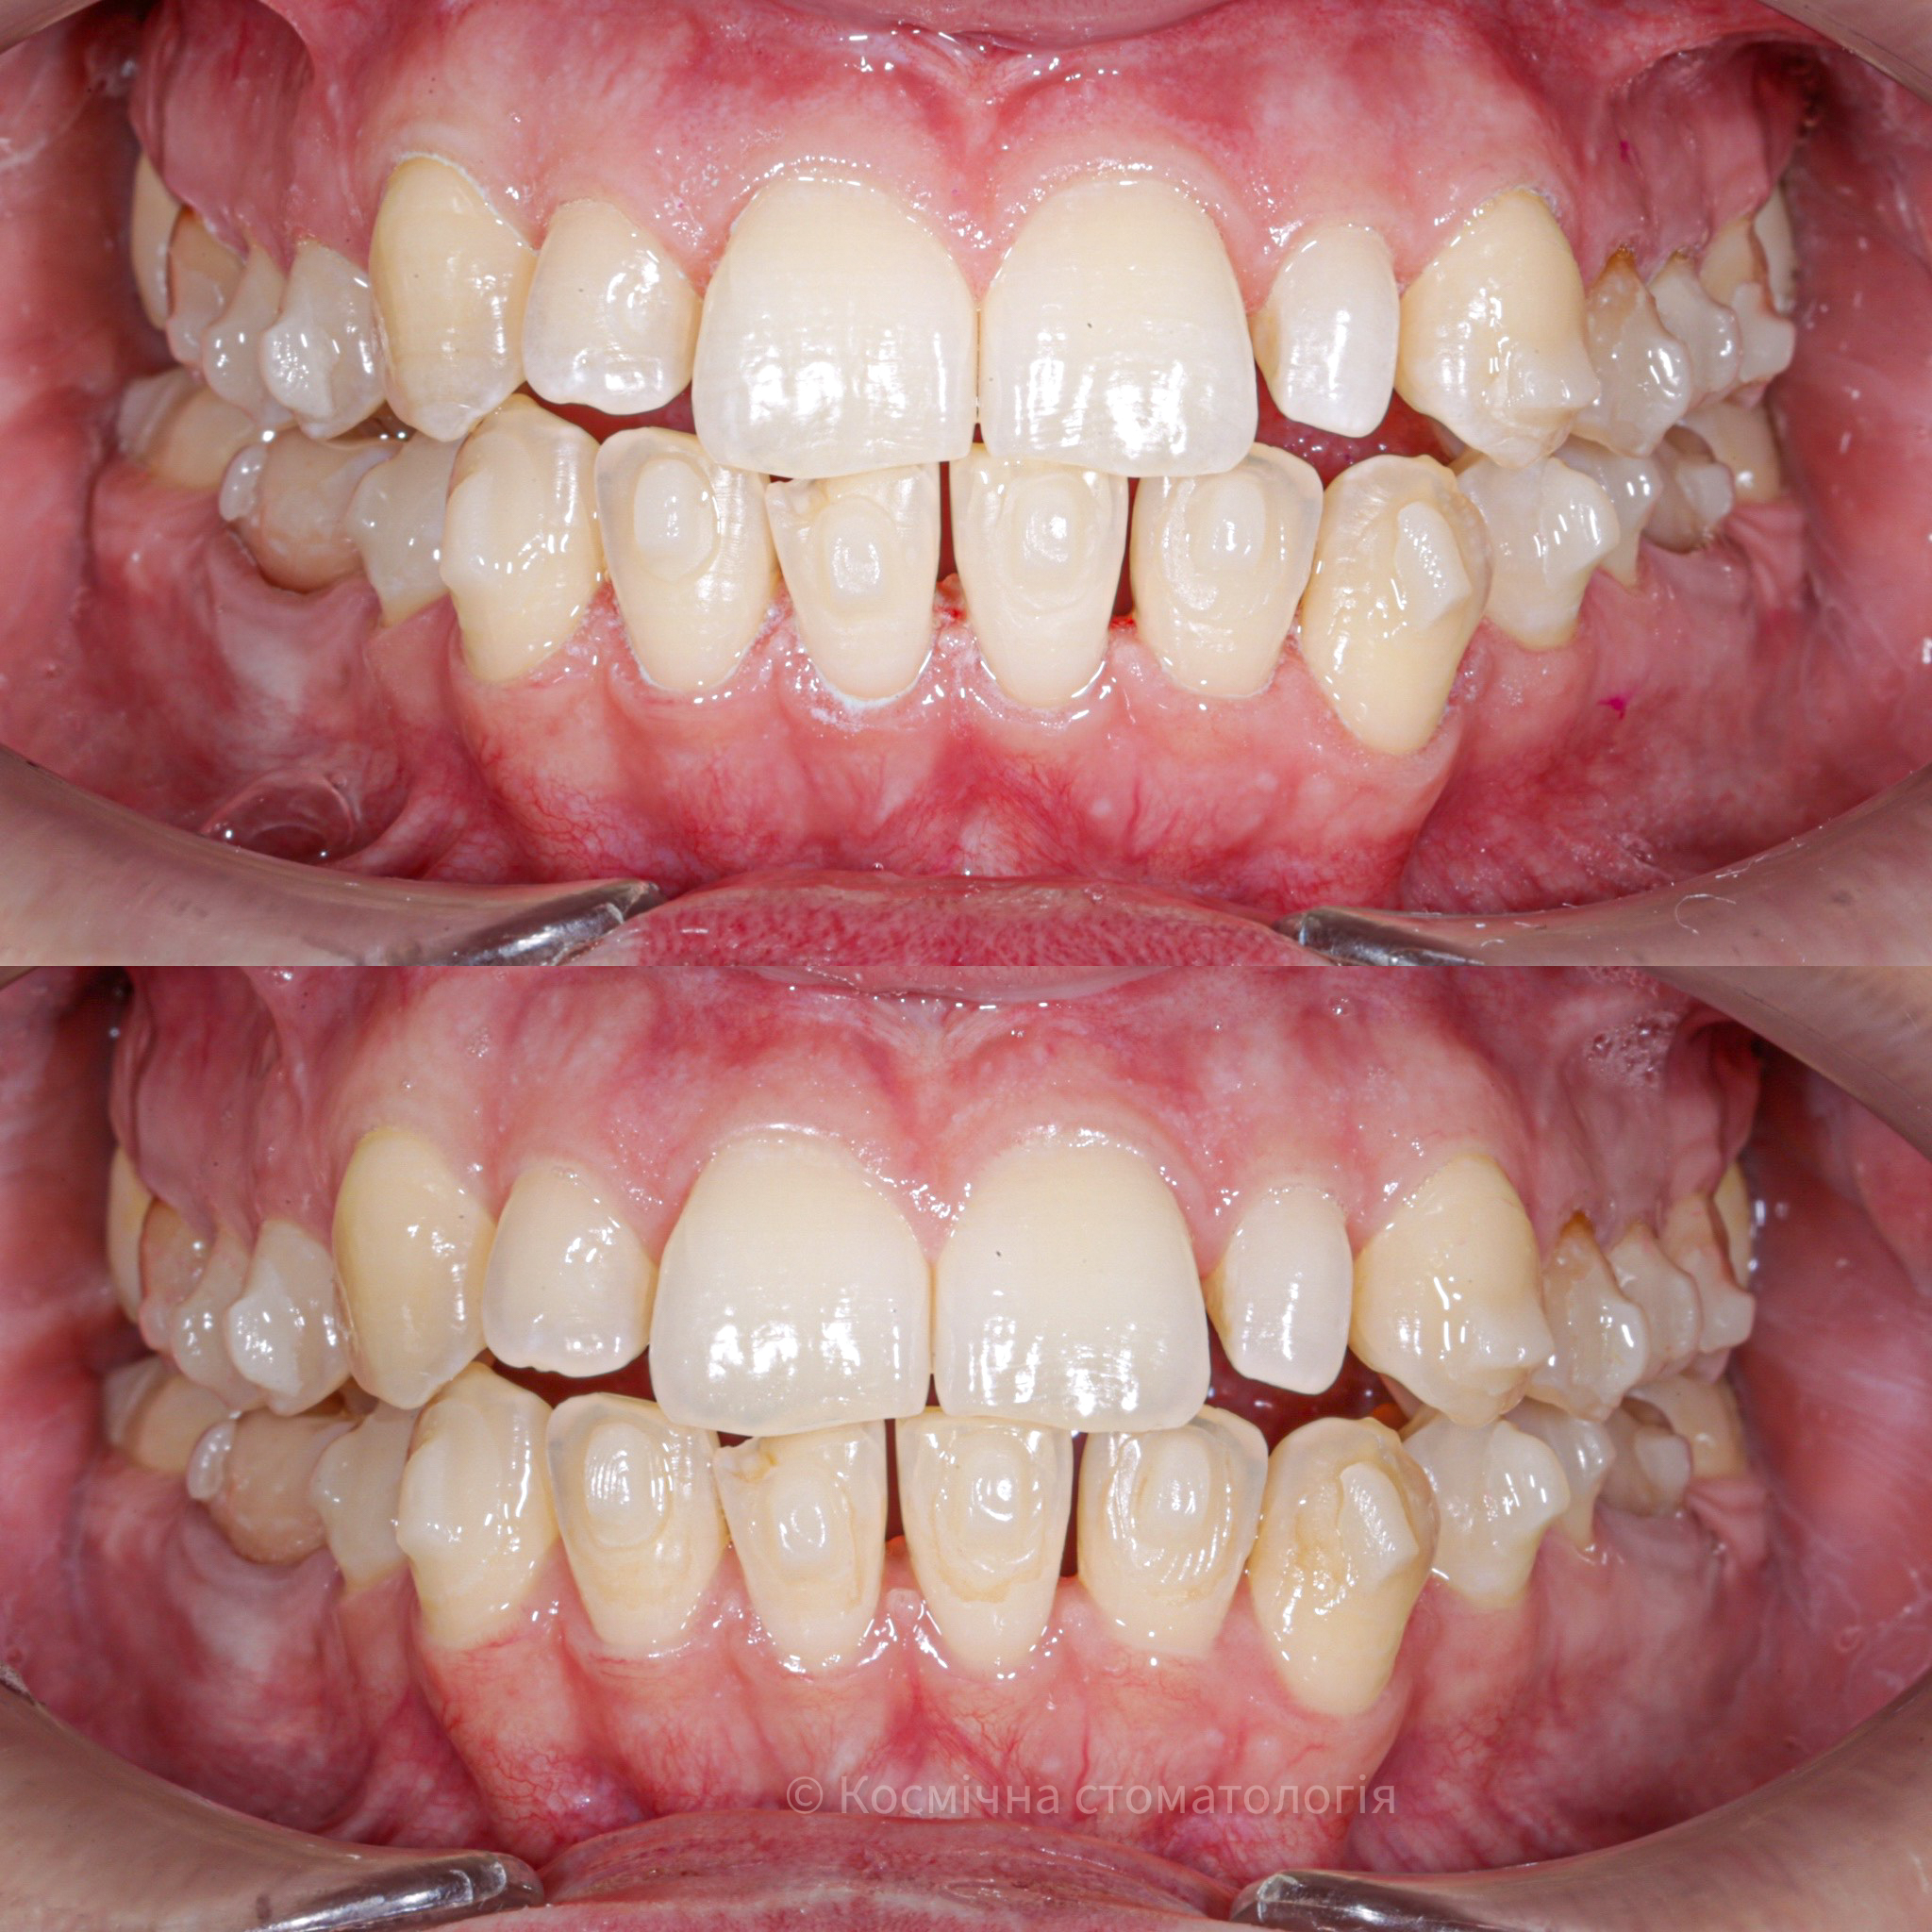

Галерея

Професійна гігієна (чистка) зубів складається з кількох етапів

• Комп'ютерна анестезія у разі підвищеної чутливості зубів.

• Зняття каменю ультразвуковим девайсом SIRONA (Німеччина) та звуковим наконечником KAVO (Німеччина) з електронним регулюванням потужності.

• Зняття каменю у важкодоступних місцях пародонтальними кюретами HU-Friedy.

• Зняття нальоту гігієнічними перлинами KaVo PROPHY pearls SUPRAGINGIVAL CALCIUM CARBONATE в індивідуальних пакуваннях із ароматом на вибір: персик, апельсин, м'ята, чорна смородина та нейтральний смак.

• Полірування швейцарською пастою Proxyt Ivoclar Vivadent для блиску та природної білизни.

• Діагностика прихованих захворювань ясен (скрінінг-тест).

• Покриття зубів фтористим лаком у місцях підвищеної чутливості;

• Ремінералізуюча терапія;

Ультразвукова чистка зубів

Зубний камінь, в залежності від місця утворення, поділяється на над- та підясенний. Найбільшу небезпеку для здоров'я зубів становить другий тип, адже це дуже сприятливе середовище для шкідливих бактерій.

При проведенні професійної гігієни застосувується ультразвуковий скалер, що дозволяе видалити зубний камінь разом з хвороботворними бактеріями з підясенних кишень.

Повітряно-абразивна чистка зубів (Air Flow)

Завдяки піскоструменевому апарату з технологією Air Flow, який використовуючи тиск повітря та води, подає на зубну емаль спеціальний абразивний склад, зуби можна очистити не лише від м’якого нальоту, а й від пігменту. Для видалення нальоту, в Космічній стоматології Драганчука ми використовуємо KaVo prophy pearls supragingival calcium carbonateneutral.

Чистка зубів щіточками та пастами

Фінальний етап професійної гігієни - полірування спеціальними щіточками та пастою, щоб усунути мікротріщини та шорохуватості, що виникли після чистки та видалити залишки нальоту, що могли в них залишитись. Це дозволяє суттєво уповільнити формування нових відкладень.

Полірування зубної емалі гумками

Кінцеве полірування поверхні зубів проводиться із застосуванням різних насадок, зокрема спеціальних гумок, що надає зубам ідеальної гладкості та блиску. Спеціальні гумові насадки відмінно справляться з наданням естетичної довершеності твоїй посмішці.